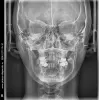

На нижней челюсти установлено два моста с обеих сторон, при этом правый нижний мост удаляется в связи с кистой опорного 47 зуба для последующей имплантации. При этом задействовать нижнюю челюсть в дальнейшем брекетами я не хочу. Трижды исправляла брекетами мезиальный прикус. Сейчас верхние зубы перекрывают нижние. Но верхняя челюсть заужена и есть дисфункция ВНЧС.

Возможно ли расширение верхней челюсти различными аппаратами притом, что на верхней челюсти с обеих сторон имеются уже два металлокерамических моста?